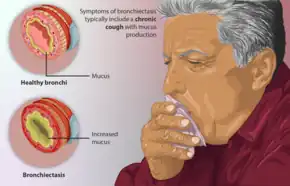

Bronchiectasis is a disease in which there is permanent enlargement of parts of the airways of the lung.[5] Symptoms typically include a chronic cough with mucus production.[3] Other symptoms include shortness of breath, coughing up blood, and chest pain.[2] Wheezing and nail clubbing may also occur.[2] Those with the disease often get lung infections.[8]

Symptoms of bronchiectasis commonly include a cough productive of frequent green or yellow sputum lasting months to years.[3] Other common symptoms include difficulty breathing, wheezing (a whistling sound when you breathe), and chest pain. Exacerbations of symptoms may occur, these exacerbations occur more frequently in advanced or severe disease.[21] Systemic symptoms, including fevers, chills, night sweats, fatigue and weight loss may be seen with bronchiectasis.[21] Bronchiectasis may also present with coughing up blood in the absence of sputum, which has been called "dry bronchiectasis."